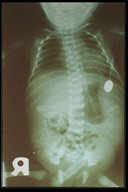

Meconium peritonitis. Scattered concentric pattern of calcification spread throughout the peritoneal cavity with intraabdominal fluid shows that there was meconium leakage sometime during fetal life.